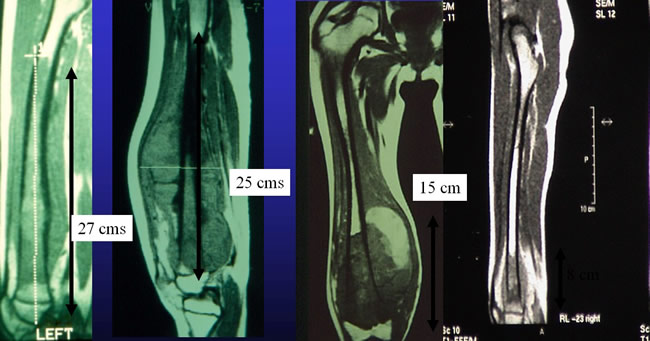

Size of the tumors

The average diameter of tumor was 12 centimeters (5-28).